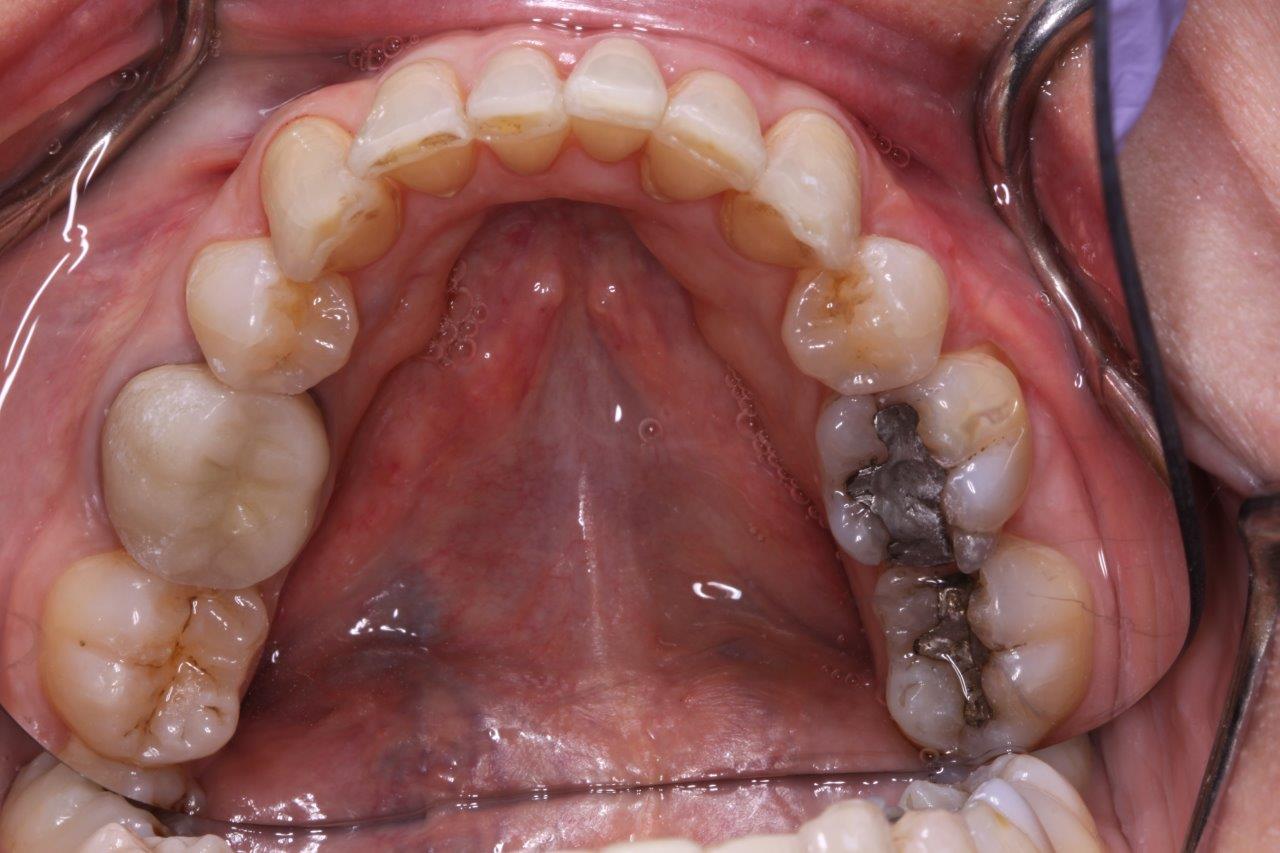

Crowns

After